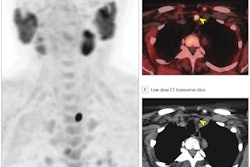

Of the entire group, 90% of patients received MRI or CT and 39% received US-FNA as part of the response evaluation three months after chemoradiotherapy. FDG-PET/CT was performed in 38% of patients.

SND was done in 130 patients (14%) due to suspicion of or confirmed residual neck disease by one or more of the imaging methods. Among patients who underwent SND, only 53 (41%) had biopsies that confirmed disease.

According to the analysis, the PPV of FDG-PET/CT for detecting residual disease was 89% compared with 65% for MRI and US-FNA. Moreover, if FDG-PET/CT showed that patients had a complete metabolic response from the treatment, they did not undergo surgery, the authors wrote.

"FDG-PET/CT significantly improved the accuracy of the detection of [pathologic-confirmed residual neck disease], thereby reducing the number of patients undergoing unnecessary SND by 22%," the group wrote.